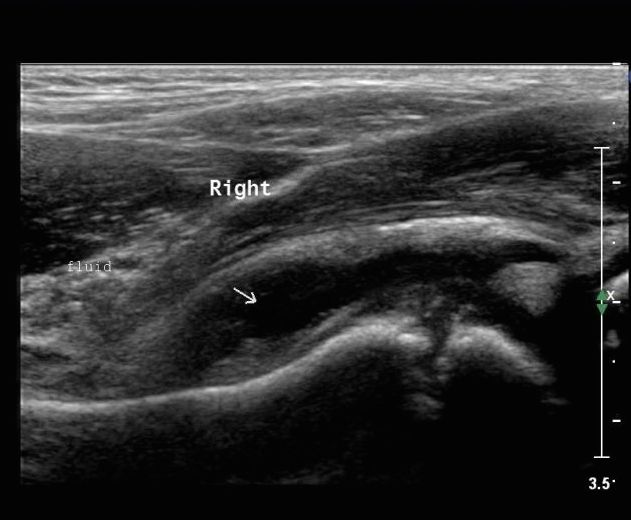

• 초음파 (US): 관절 삼출액(joint effusion) 확인 (필수)